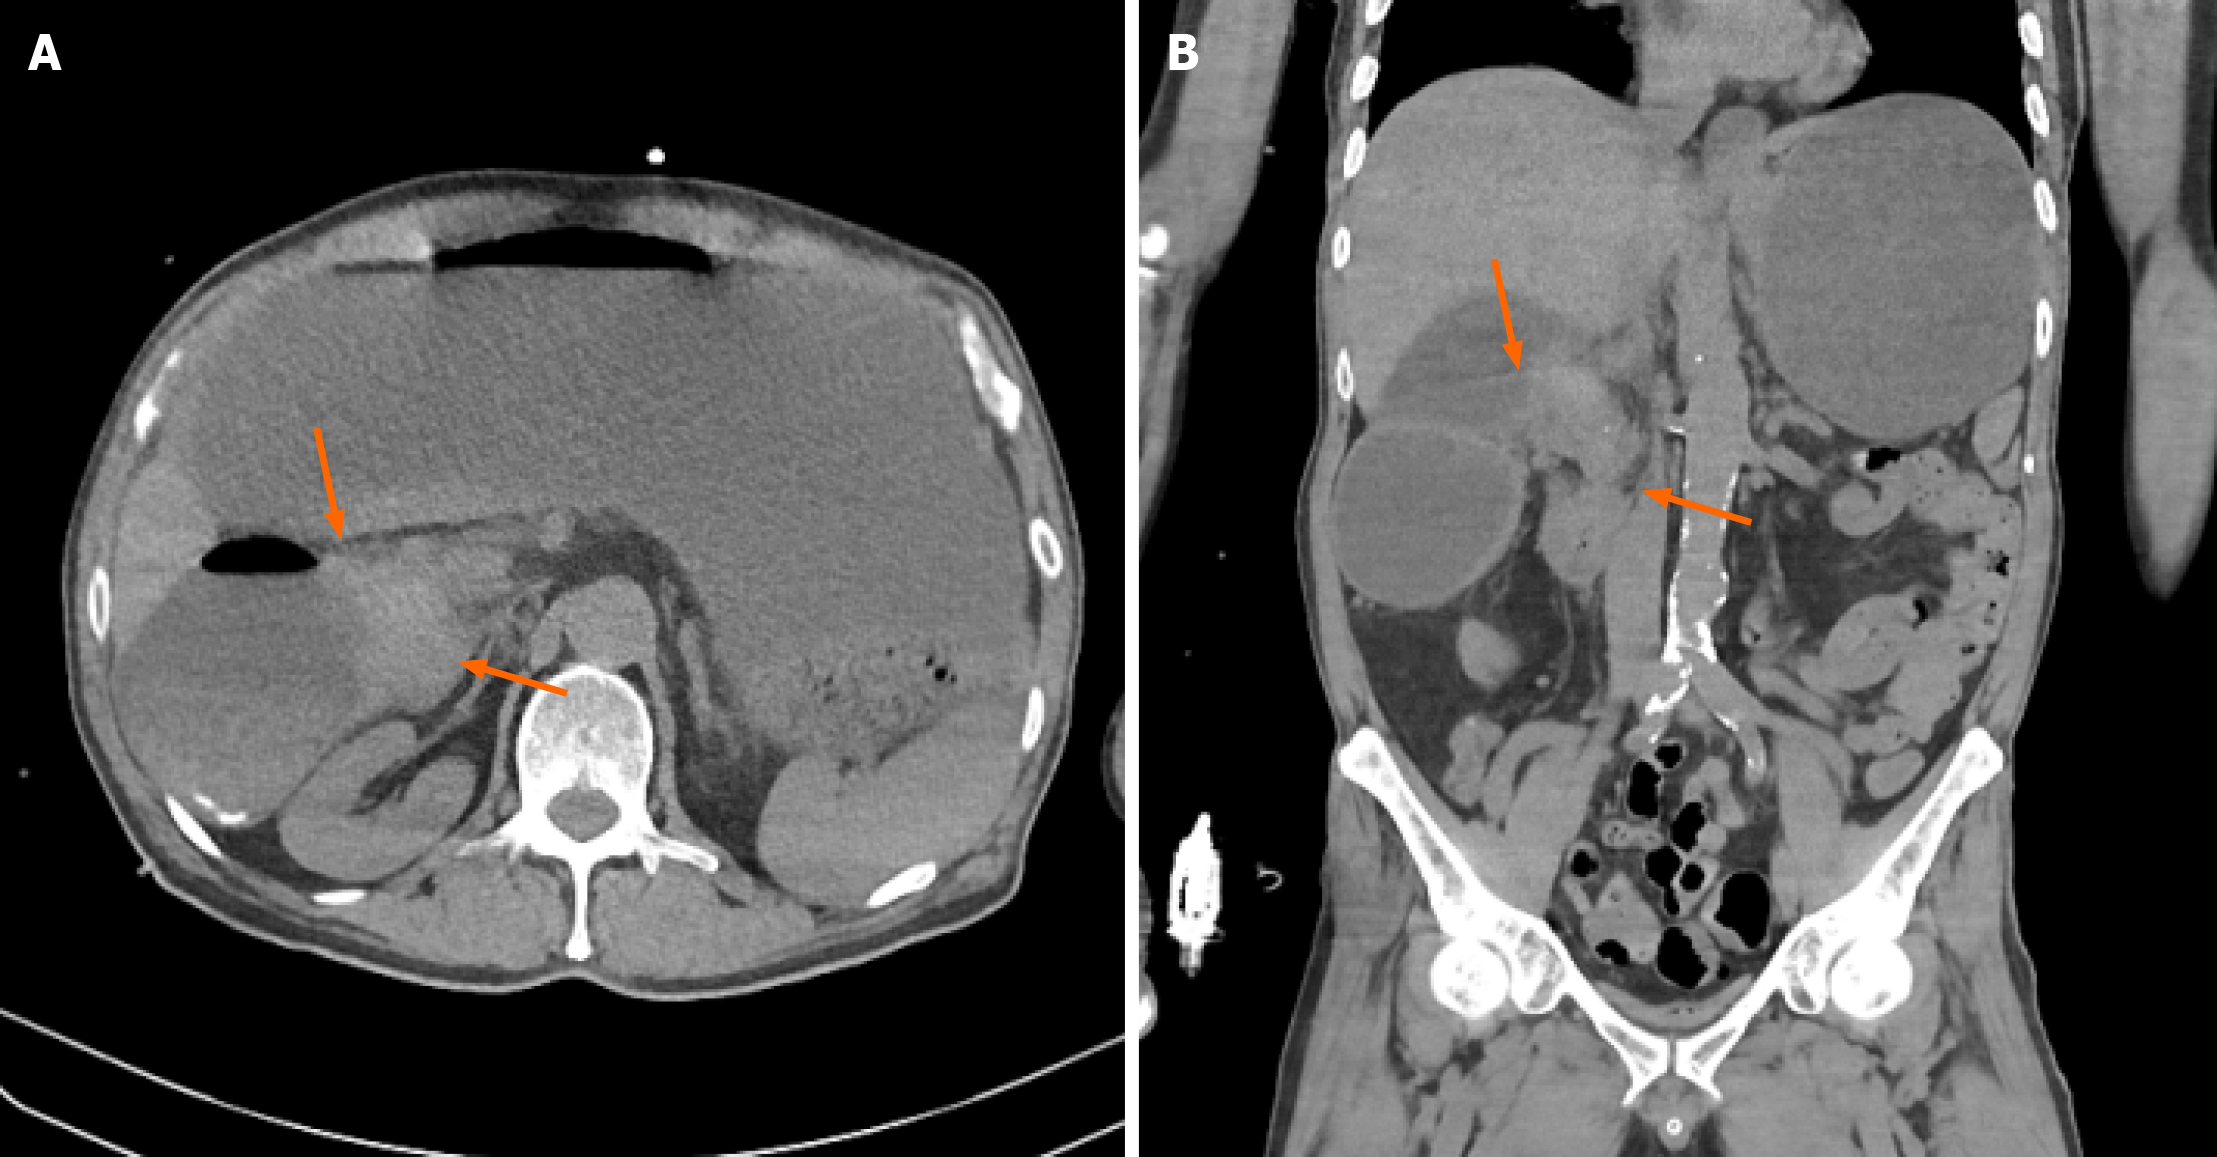

Figure 1 Computed tomography imaging findings.

Non-contrast abdominal computed tomography scan showing a mass-like lesion (orange arrow) causing a severe luminal stricture in the second portion of the duodenum and marked dilatation of the stomach and first portion of the duodenum. A: Non-contrast axial image; B: Non-contrast coronal image.